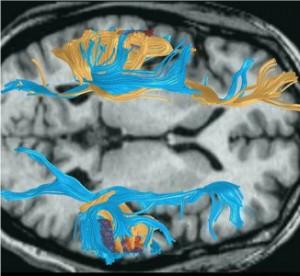

Diffusion Tensor Imaging (DTI) allows scientists to see the white matter fiber tracts that form the major connections among different parts of the brain. Essentially this allows researchers to see a road map of the brain.

There does not appear to be any one pattern for dyslexia, but researchers have found evidence of marked structural differences in dyslexic brains. The image displayed shows a comparison between the brain pathways of a dyslexic man (depicted in blue), and another adult with a very typical brain structure (shown as gold). While the dyslexic subject has less extensive connectivity in the left hemisphere, overall the brain pathways are more evenly distributed and are far more robust in the right hemisphere.